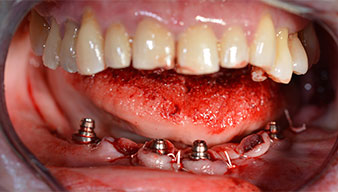

A three-dimensional cone beam computed tomography scan (CBCT, Planmeca) was performed to aid planning and minimize risks. This revealed that the quality and quantity of the available bone were sufficient for the surgery and immediate restoration using the Fast & Fixed method. Following the protocol for this concept, the implants are inserted at 35, 32, 42 and 45. Angling the distal implants by up to 45° shifts the emergence profile to posterior and generates a larger support polygon (Fig. 3).

Angled abutments (35°) were screwed in to compensate for the divergence of the distal implants, with the result that the emergence profile of all implants was as perpendicular as possible to the bite plane. This is a prerequisite for occlusal placement of the provisional and subsequently the permanent denture (Fig. 15 and 16).